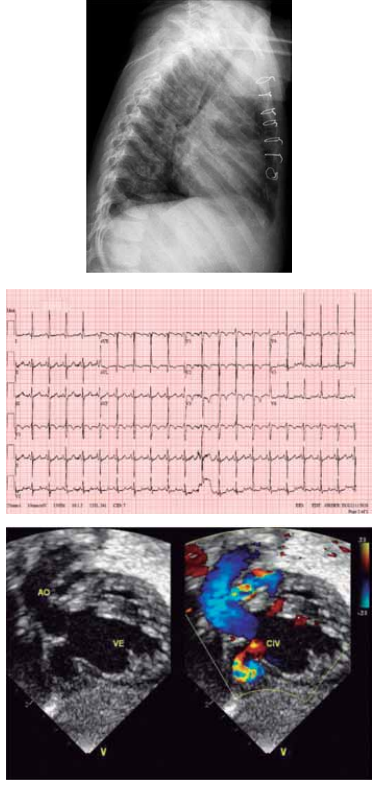

Paciente de 1 mês de idade foi admitido em Unidade de

Terapia Intensiva, acompanhada de cuidadora de abrigo,

devido à piora da cianose. Mãe drogadita perdeu guarda

dos 6 filhos. A saturação na Unidade manteve-se estável,

ao redor de 84%, sem insuficiência cardíaca congestiva,

em uso de propranolol; foi acompanhado no ambulatório

até os 2 anos de idade e realizada intervenção cirúrgica

cardíaca. Com base nos seguintes exames complementares, quais seriam, sucessivamente, a cardiopatia congênita provável, a cirurgia realizada aos 2 anos de idade

e a cirurgia atual para a qual foi convocada?

(Arquivo pessoal; imagens usadas com autorização)